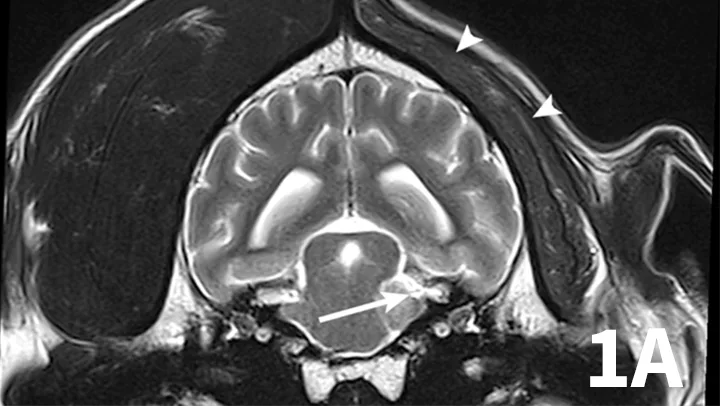

Nerve sheath tumors (NSTs) are perhaps the most common cause of chronic, progressive peripheral cranial nerve disease in older dogs. They arise from Schwann cells or pericytes, are typically slow growing, and are invasive to surrounding nervous system tissue. Metastasis is a rare event associated with NSTs. Whereas they most commonly affect the brachial plexus and lumbosacral plexus, NSTs also can arise within cranial nerves, with the trigeminal nerve most frequently affected. Clinical signs of trigeminal NSTs are ipsilateral to the NST and include unilateral masticatory muscle atrophy, facial hypalgesia, reduced corneal sensation, and Horner syndrome.1 Magnetic resonance imaging (MRI) is the modality of choice for identifying lesions. On MRI, NSTs are mass-like, tubular structures that are contiguous with a nerve (Figure 1).2 Lesions are often hyperintense (bright) on T2-weighted images (T2WIs), indicating high water content from edema, neoplastic cells, or inflammation, and strongly contrast enhance on T1-weighted images (T1WIs) following the delivery of gadolinium, suggesting a blood–nerve barrier breakdown or neoangiogenesis.

Transverse T2WI (A) and postcontrast T1WI (B) from a 10-year-old golden retriever with a 6-month history of left masticatory muscle atrophy. Adjacent to the left lateral pons is a mass-like lesion (arrow) confluent with the left trigeminal nerve that is T2-hyperintense and contrast-enhances on T1WI. There is profound atrophy of the left temporalis muscle (arrowheads), which is likewise T2-hyperintense with subtle contrast enhancement on T1WI. These findings are consistent with a nerve sheath tumor of the proximal trigeminal nerve with secondary neurogenic muscle atrophy.